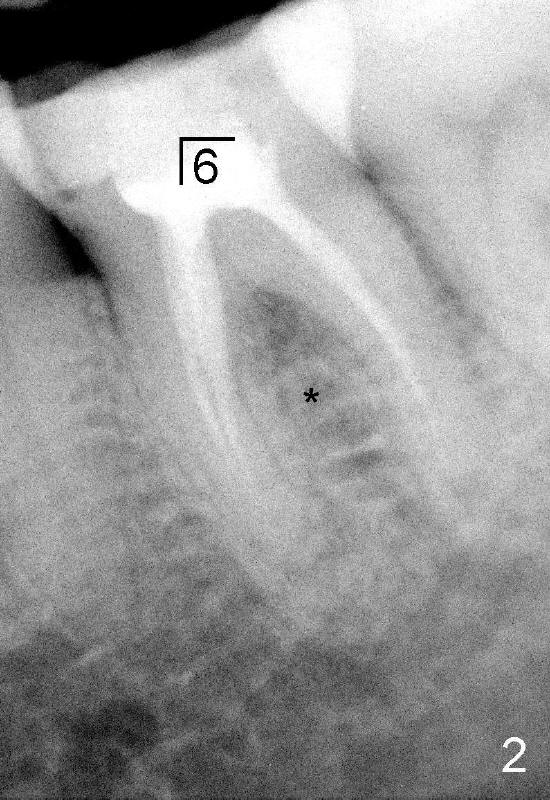

A 41-year-old lady fractures the crown of the lower left 1st molar (Fig.1.2). After removal of the remaining crown (Fig.3*) and exposure of the top of the septum, a pilot drill (D, 1.5 mm) is used to initiate the osteotomy. Drills with increasing diameters could be used to enlarge the osteotomy while the roots are in place (Fig.4: white rectangular outline).